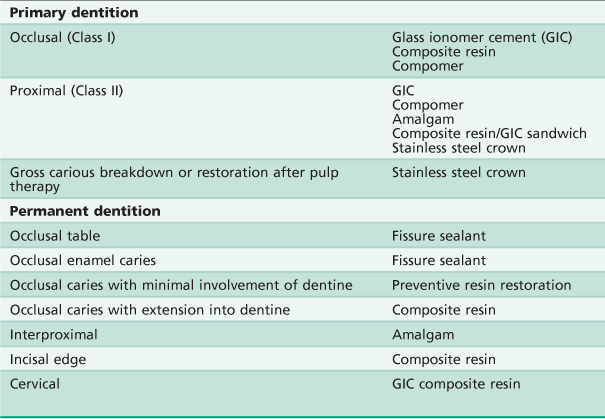

/trab07131/tab01t07131.jpg)